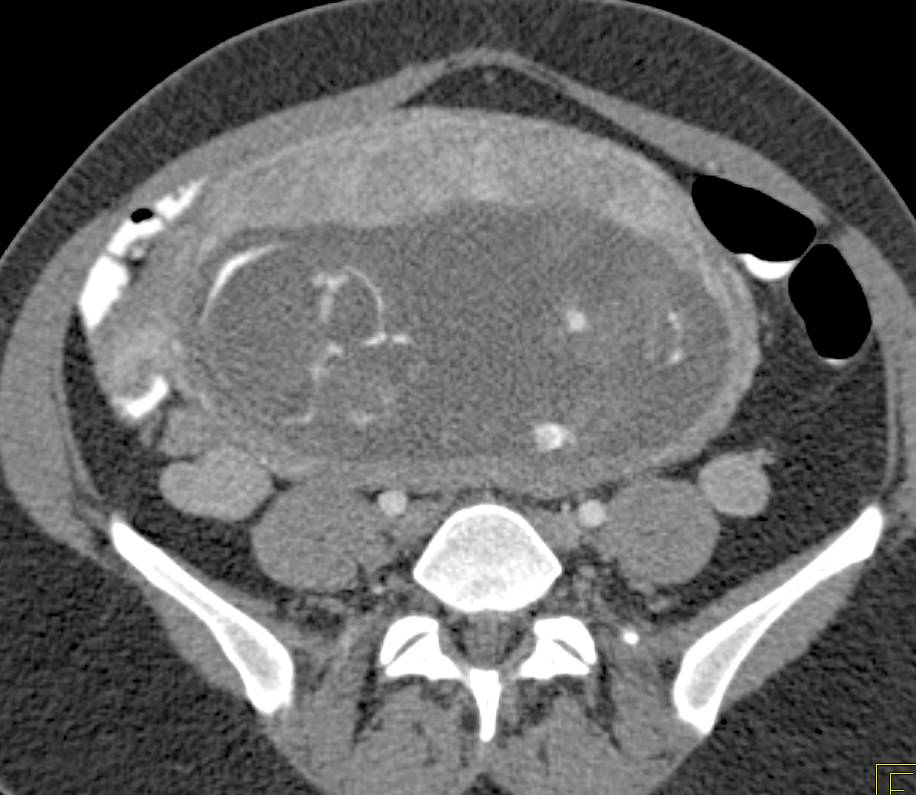

Bicornuate uterus